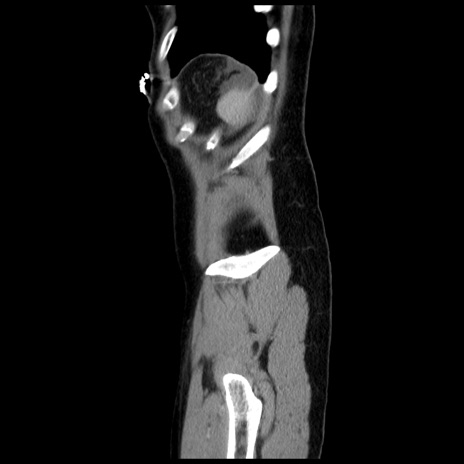

症例10(矢状断像)

【症例】 50歳代女性

【主訴】 腹痛

【現病歴】前日生レバーを食べた。今朝に排便あり。 昼前に突然発症の腹痛を生じ、当院救急外来を受診した。

【既往歴】 子宮筋腫にてで子宮全摘後

【身体所見】 意識清明、腹部:平坦、軟、下腹部やや左を中心に圧痛・反跳痛あり、筋性防御あり

【データ】WBC 7800、CRP 0.07